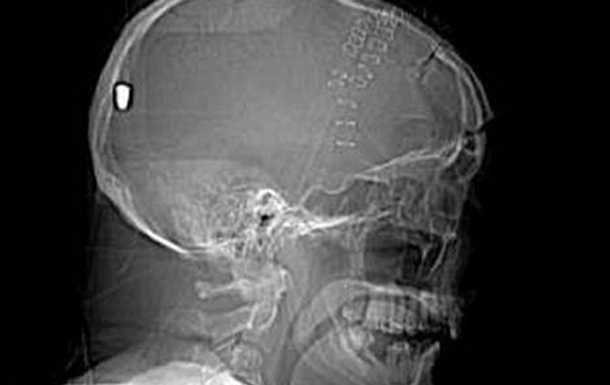

Man shot in head felt bullet only 4 years later

Man shot in head felt bullet only 4 years later. (SUPPLIED)

A 35-year-old man who walked around for five years with a bullet lodged in the back of his head says he suspected for a while something was there but only went to doctors after he started getting headaches.

Robert Chojecki was partying on New Years Eve five years ago in the German town of Herne when he was hit with the .22-caliber bullet. Doctors removed it this week from between his skin and skull.

Police say the bullet may have been fired in celebration. Doctors say he should have no problems now that it has been removed.